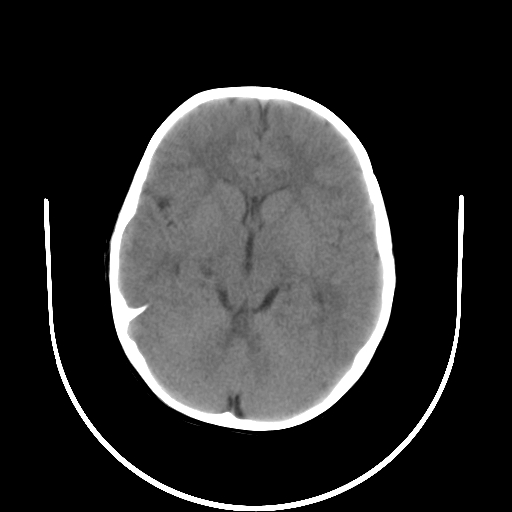

以下是引用拾荒者在2009-10-17 18:38:00的发言:[br]鼻面部皮下积气,右侧睑缘及眼球壁高密度异物影,左侧眼球壁晶状体内侧缘处是圆形低密度影。低密度异物?应提请眼科医生注意。